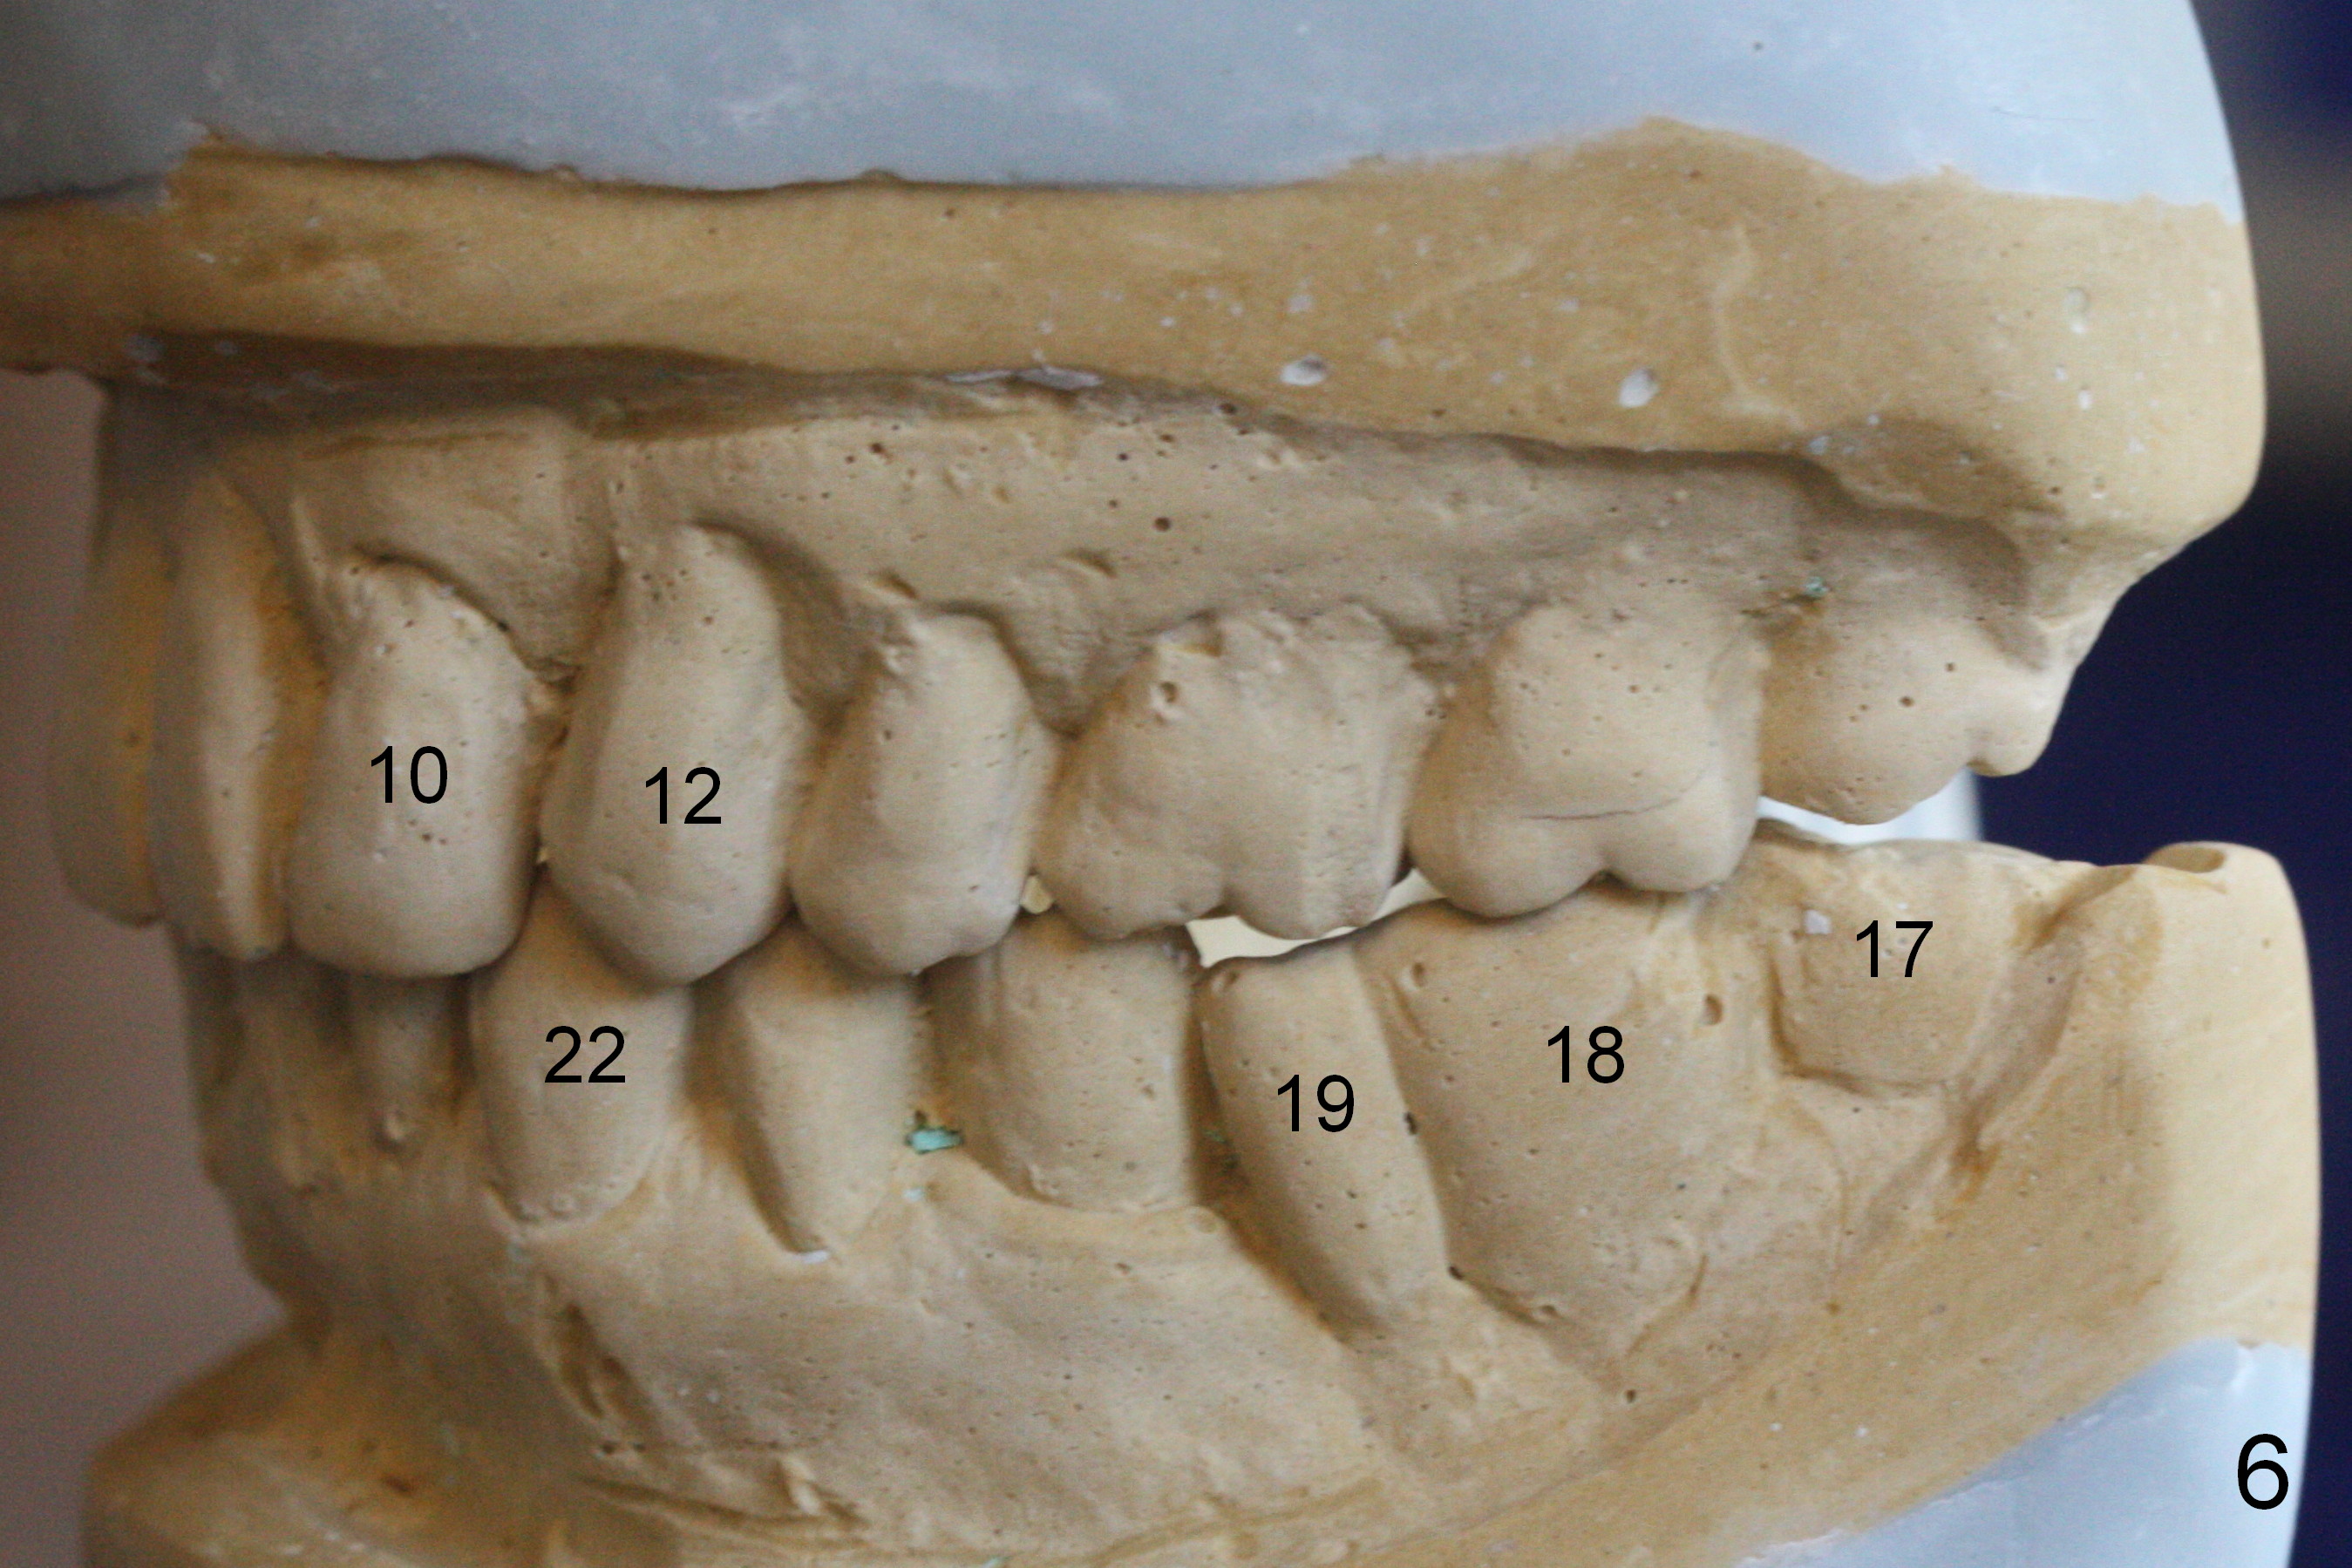

A 82-year-old man has pain in the lower left bridge. There is a buccal apical fistula associated with the tooth #17 (Fig.1). An immediate implant will be placed at #17 after bridge removal (Fig.2,3 blue). Once it osteointegrates, it will be used an anchorage (direct (instead of indirect), most efficient) to upright the tooth #18 (change the longitudinal axis from red line to purple one (Fig.4); white circle: center of resistance (rotation)). Then an implant will be placed at #19 (white rectangle).

Take Alginate impression and keep it moist. It will be used as a stent for temporization later on. After the tooth #17 is extracted with Clindamycin treatment, a FC dummy implant (5x9 mm) will be placed, followed by 6x4(2) mm abutment (Fig.3,4 pink). If there is severe vertical height issue, change to Magicore. Due to schedule conflict, prepare UF for this case instead.

One of the patient's daughter feels that the treatment is too complicated. She would like to have the 2nd molars extracted and implants at the 1st and 2nd molar sites (from Fig.5,6 to 7-9). Since the upper canines are missing (Fig.5,6), the final occlusion will be Class II posteriorly (Fig.8,9).